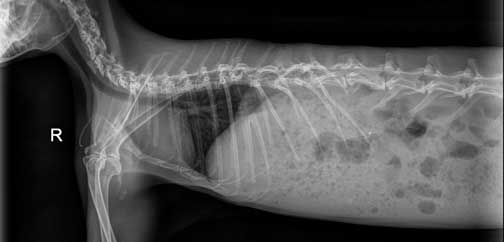

Any animal with a traumatic injury like a broken bone can have a problem elsewhere from that trauma that is not apparent. This is why we take a radiograph of the rest to the patient, especially the chest. The chest is towards the left, with the dark are being the lungs, and the white structure the heart.

You just never know what you are going to find when you radiograph a rabbit! This one has a urinary bladder filled with stones! Click here to learn more about bladder stones in other species.

This one has a problem with calcium sludge in the urinary bladder. Our Calciuria page has more details.

The heart and lungs (within the red circle) are tiny compared to the size of the abdomen. This ratio between lungs and abdomen is much smaller than in other animals, and needs to be closely watched during anesthesia.